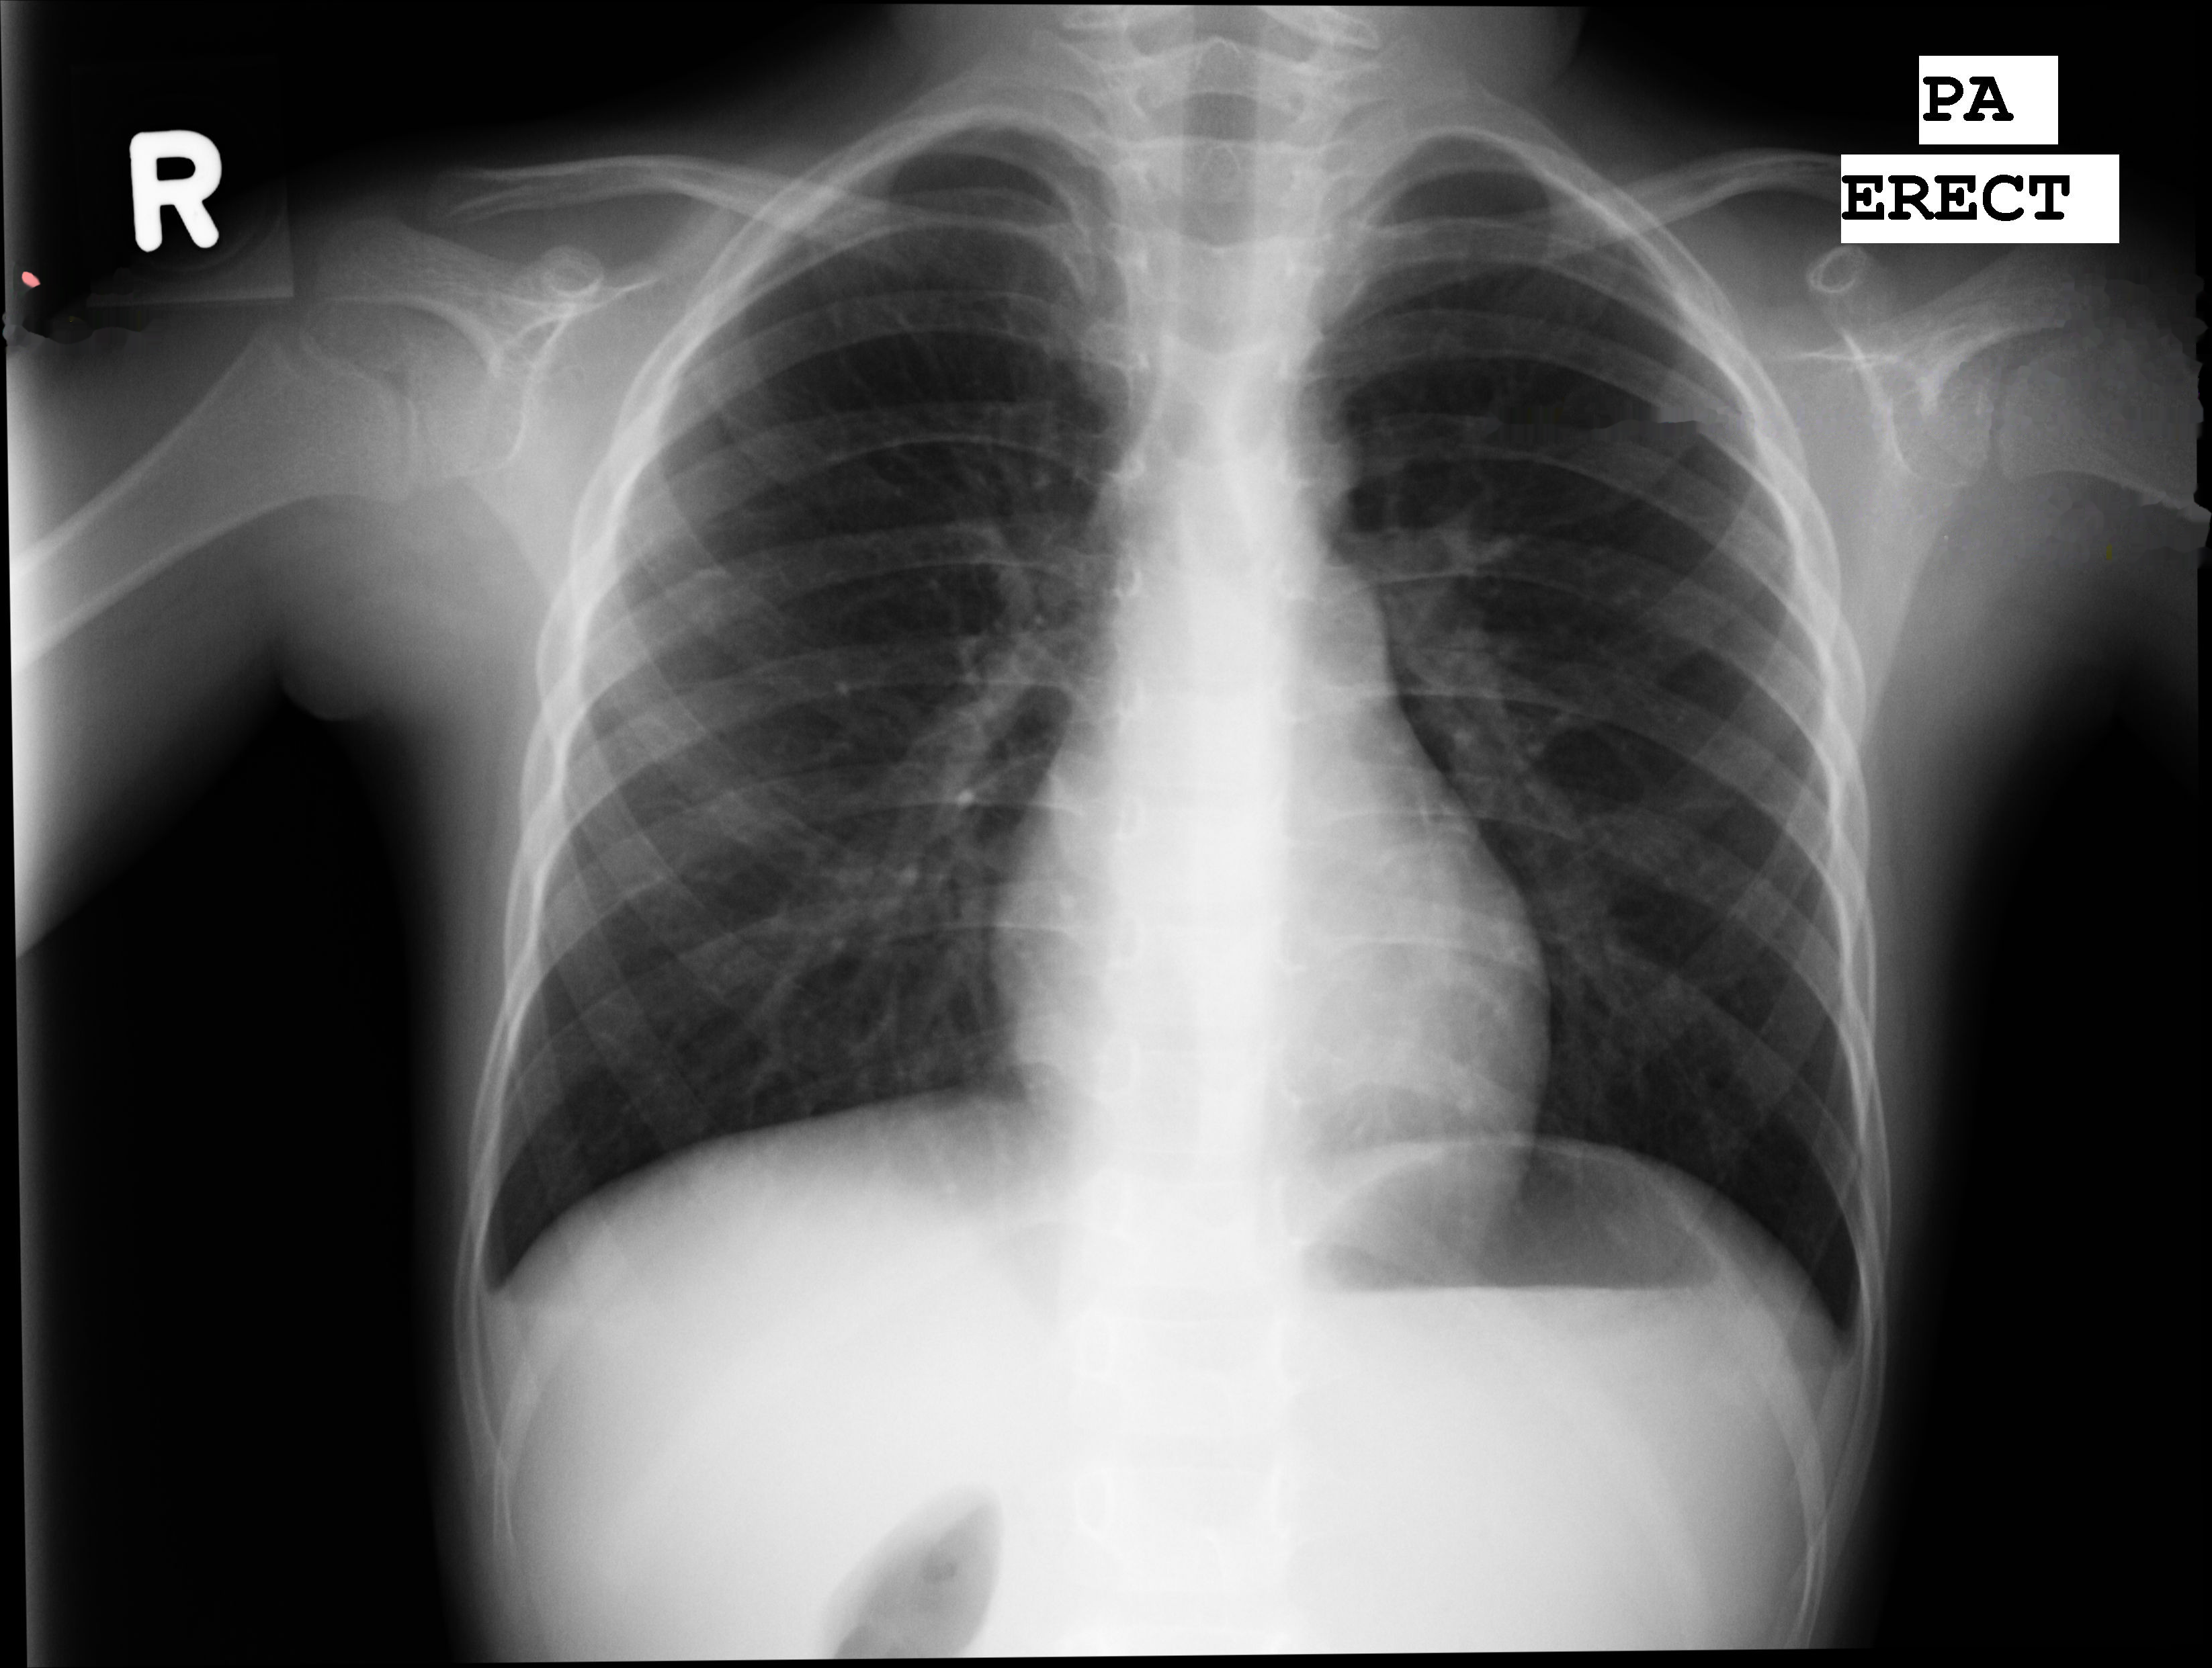

Once the text has been localized there are two possible options for removing it: image interpolation or masking. Image interpolation, or inpainting, is a magical tool in image processing where the image appears as if the text never existed, whereas masking is simply blanking out the image where the text used to appear. The choice between the two is primarily based on how you believe the artifacts introduced by either method will affect your model’s ability to learn. The last part of the text removal phase is to crop only the x-ray from the background. Check out the results below!

Fig 4a. - Inpainting